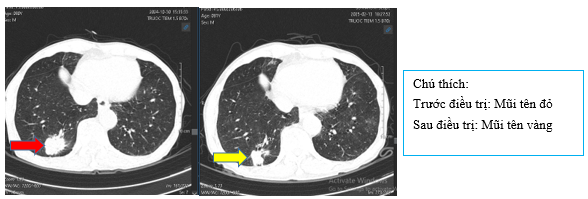

Hình 7: Hình ảnh các hạch trung thất trước điều trị lớn nhất ~16x12mm (mũi tên đỏ) giảm nhẹ sau điều trị còn 15x12mm (mũi tên vàng)

- Chụp CT bụng sau điều trị:

Hình 9: So sánh phim chụp CT bụng trước điều trị nốt tuyến thượng thận ~11mm (mũi tên đỏ) đã giảm nhẹ kích thước sau điều trị còn ~9mm (mũi tên vàng)